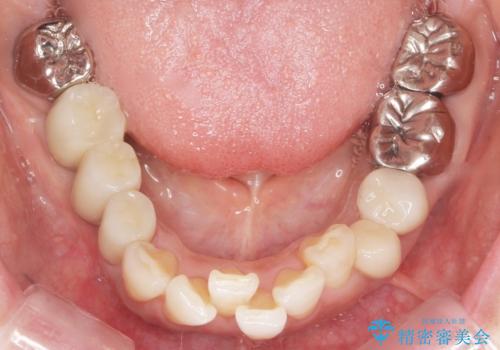

保存不可能な歯を抜去後、インプラント治療と根管治療を行いました。

他にも予後不良な歯があり治療を提案しましたが、ご予算もありご希望されませんでした。

インプラントへの悪影響に関しても説明し、了承頂いた上で治療を行いました。

奥歯でしっかり咬むことができるようになり、大変喜んで頂けました。